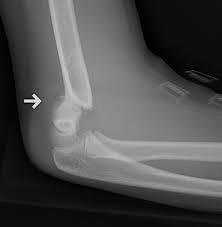

What is radial head subluxation?